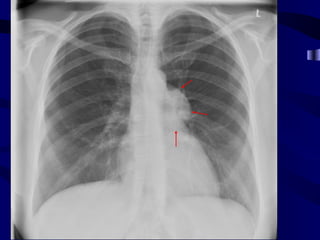

Unilateral Hilar Enlargement •Causes of hilar lymphadenopothy – Neoplastic, e.g. spread from bronchial carcinoma, primary lymphoma – Infective, e.g. tuberculosis – Sarcoidosis (rarely unilateral) • Causes of hilar vascular enlargement – Pulmonary artery aneurysm – Poststenotic dilatation of the pulmonary artery